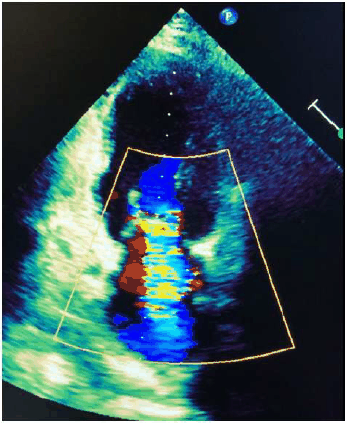

Mulher de 49 anos procurou o médico de família e comunidade, apresentando queixa de dispneia progressiva aos esforços, sendo identificado sopro cardíaco ao exame físico.

Realizou o ecocardiograma reproduzido abaixo.

Considerando esse caso,